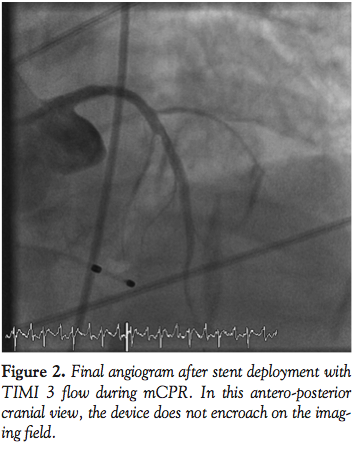

epinephrine and atropine before her pulse was restored. She suffered recurrent cardiac arrest in the CCL and resuscitation efforts were initiated with CPR, epinephrine, and atropine. The LUCAS device was placed and mCPR commenced. An IABP was placed via the right femoral approach and a temporary transvenous pacemaker placed via the right femoral vein. Angiography was performed via left femoral access during mechanical CPR. Her mid LAD was occluded with TIMI 0 flow (Figure 1). Balloon angioplasty was performed promptly with rapid restoration of TIMI 3 flow and placement of a bare-metal stent in the mid LAD (Figure 2). The semi-radiolucent LUCAS device was not visible on coronary angiography or during PCI in a steep right anterior oblique cranial projection. Despite maximal support with an IABP and multiple vasopressors, the patient manifested no significant myocardial function and expired in the catheterization laboratory after mCPR was discontinued.

Fluoroscopic and cineangiographic imaging during mCPR with the LUCAS device requires few significant adjustments. The images presented here represent one center’s experience and diagnostic images were obtained in all cases. Anterior-posterior projections are limited by the height and radio-opacity of the LUCAS drive unit over the patient’s chest. Straight right and left anterior oblique views provide adequate visualization despite the back-brace component of the device being visible on fluoroscopy. As evidenced in Cases 1 and 4, significant cranial angulation (>30°) can provide coronary imaging without visual encroachment by the device components.

In animal models, cerebral blood flow during CPR is improved with mCPR,15 and mCPR devices provide significantly higher coronary perfusion pressures than manual CPR.16 Coronary flow assessment has been reported in both animal models and human subjects.16,17 In 4 out of 6 patients studied by Larsen et al with TIMI 3 flow during mCPR, invasive measurements documented adequate coronary perfusion pressure gradients. In the present experience, coronary flow during mCPR is pulsatile, but classification by TIMI grade is readily apparent. In Cases 1, 4, and 5, the PCI procedure itself was performed during mCPR compressions (Figures 1, 2, 8, and 10).